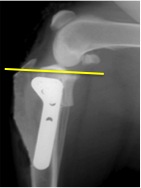

手術は様々な方法がありますが、当院ではTPLO(脛骨高平部水平化骨切術)を実施しております。 TPLOは前十字靭帯断裂に対する最新の手術法の1つです。 脛骨を一部骨切りし、回転させることによって斜めに傾いているところを平らにし、 脛骨が前に出る力を無くしてあげようという手術法です。

他の手術方法ではワイヤーや他の靭帯を用いて前十字靭帯の再建を試みますが、 TPLOは膝の機能の安定化を目的としている手術法です。 そのためTPLOは前十字靭帯の完全断裂だけでなく部分断裂の治療法としても有効であり、 活発に運動ができるようになるまでの期間を従来の手術法よりも短縮させ、 関節内の変化を最小限に抑えることが出来ます。 特に、長期のリハビリテーションや術後管理が困難な大型で活動的な犬の治療法として最適です。 実際に手術を行なった子のレントゲンです。斜めだった脛骨が平らになっているのが分かります。